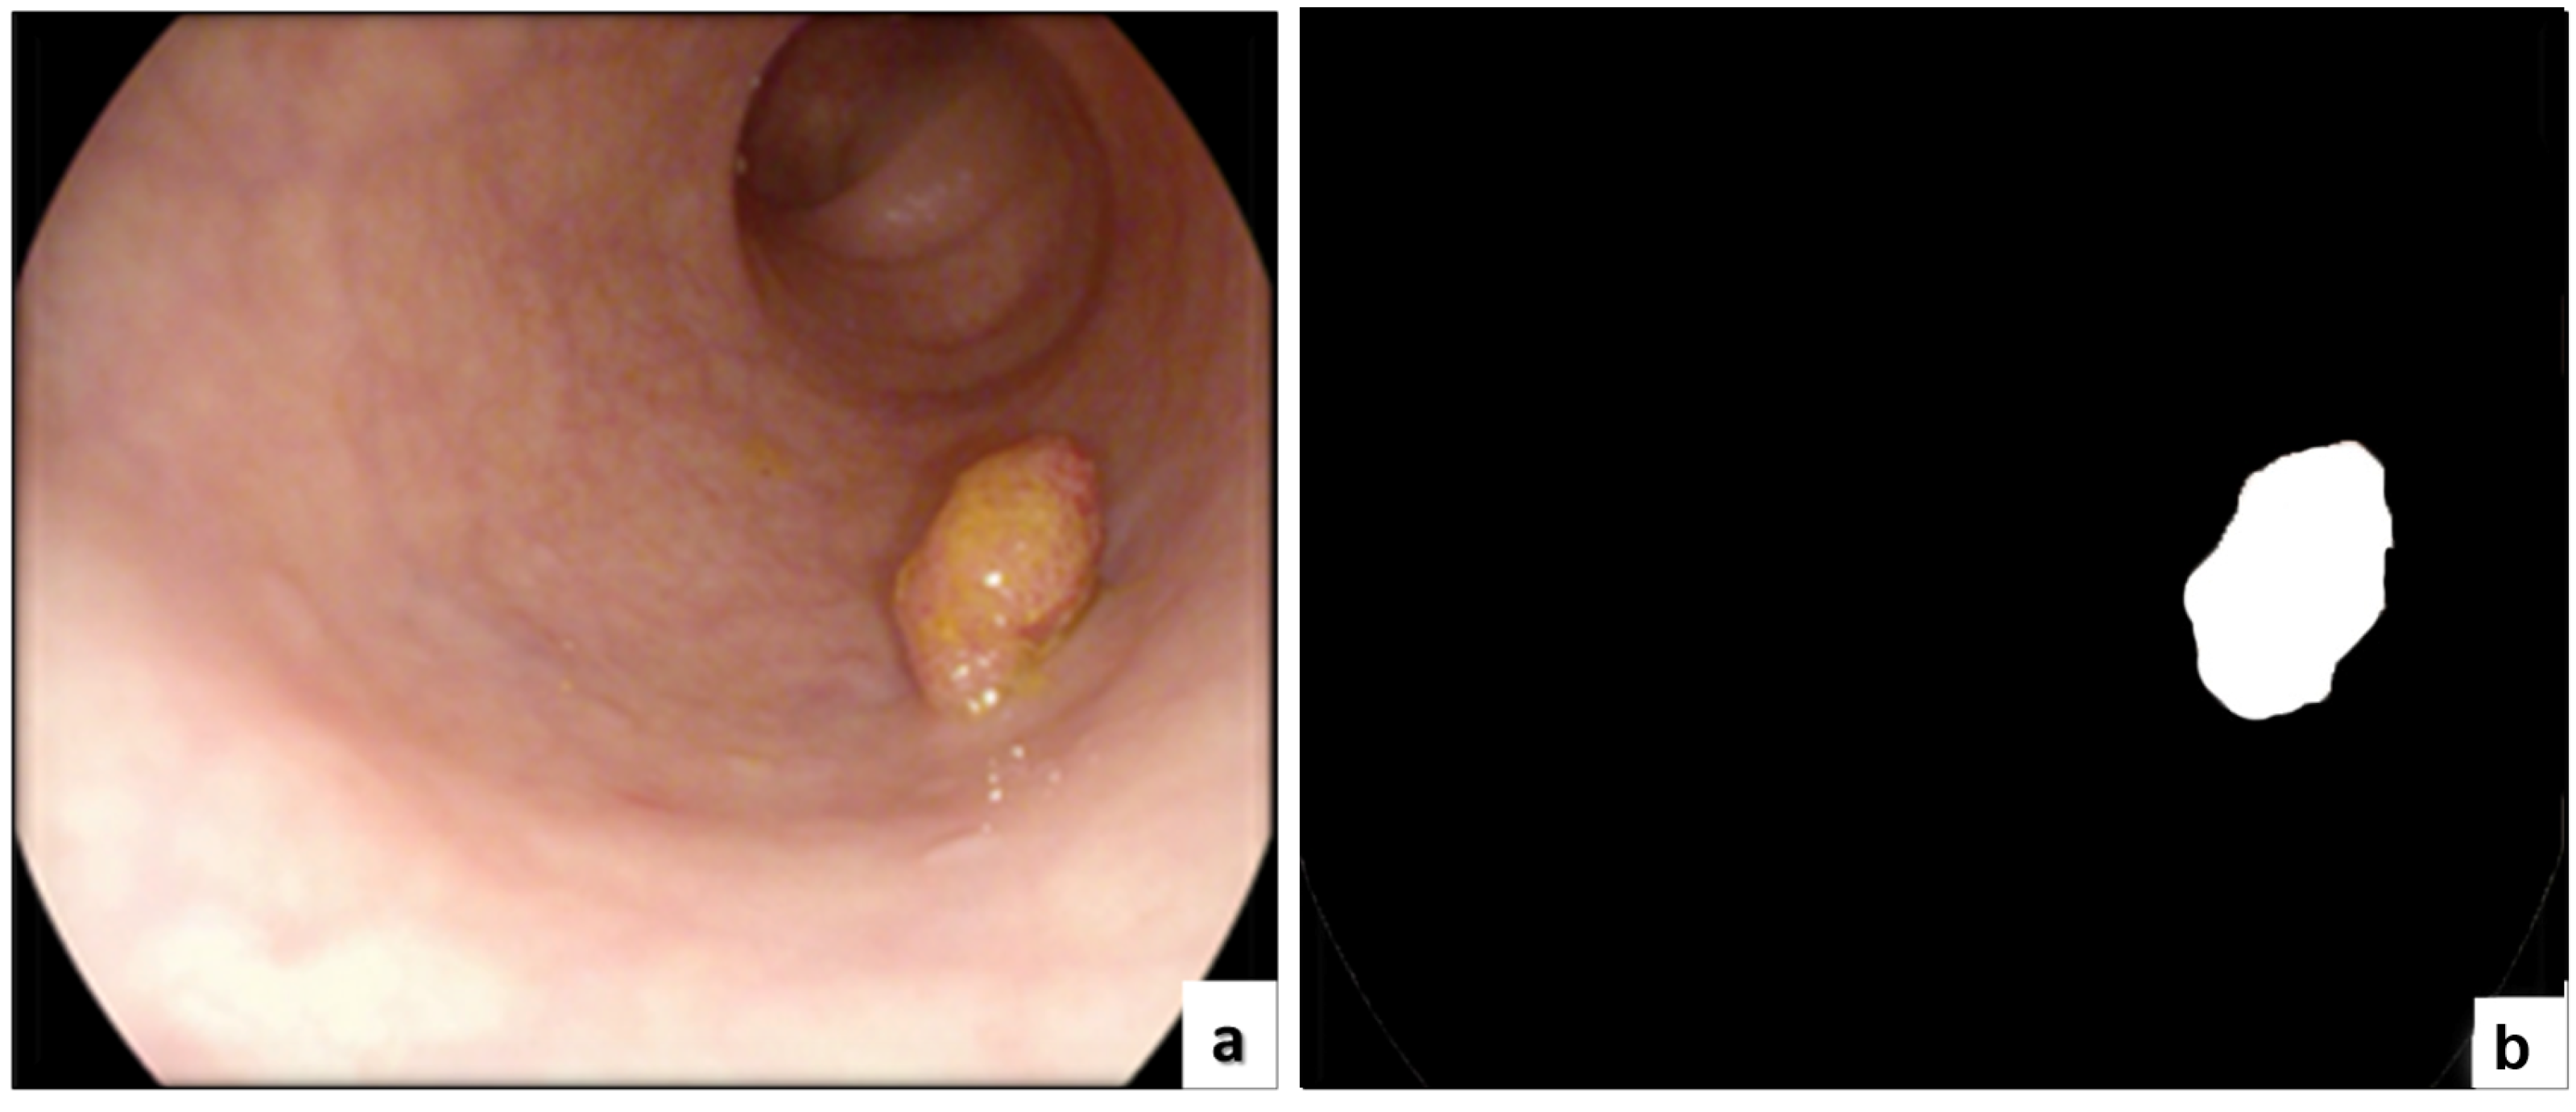

| Jha et al. [60] | Kvasir-SEG | 1000 | Various resolutions | Polyp segmentation | Colonoscopy |